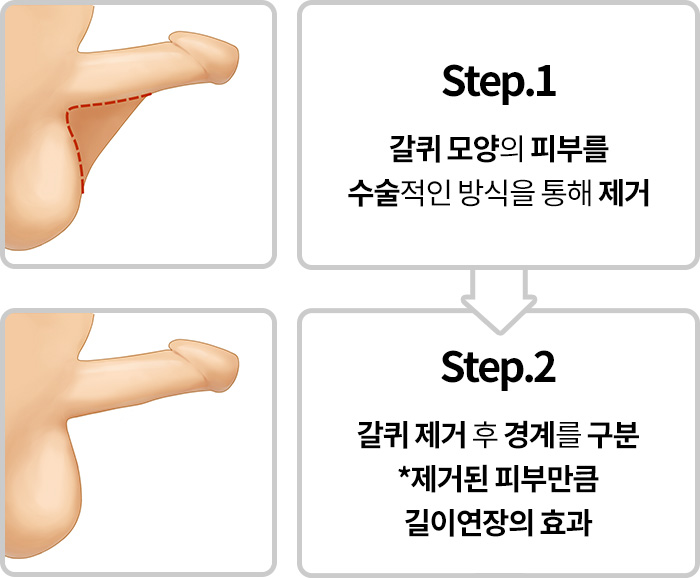

음낭갈퀴

음경에서 음낭으로 이어지는

피부가 마치 갈퀴모양처럼

발달되어 있는 경우

음낭갈퀴

음경에서 음낭으로 이어지는

피부가 발달되어 길이가 짧아 보이는 만큼

발달된 피부조직을 제거하는

수술을 통해 효과를 기대해볼 수 있습니다.